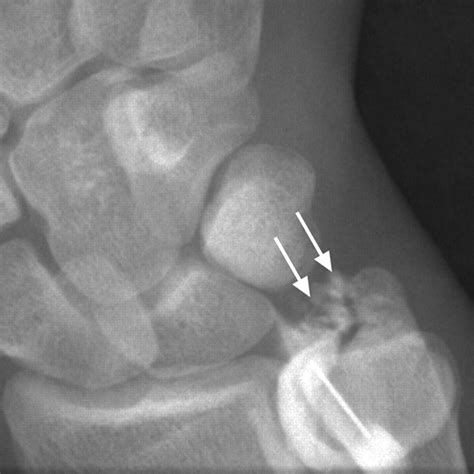

• Imaging Tests: X-rays, MRI, or CT scans may be ordered to visualize the knee joint and confirm the diagnosis. MRI is particularly useful for detecting soft tissue injuries like cartilage tears.